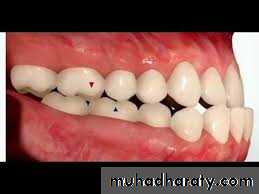

according to british standards incisor classification, in class III malocclusion the lower incisor edges lie anterior to the cingulum plateau of the upper incisors. the overjet is reduced or reversed.According to Angls classification , in class III the mesiobuccal cusp of the lower first molar occluds mesial to the class I position.

5- reduced or reversed overjet